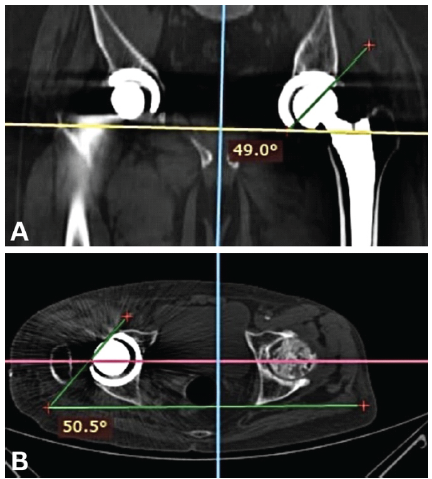

Anteroposterior pelvis and cross-table lateral hip radiographs were obtained on the 2nd post-operative day, along with a CT-scan (from L4 vertebra to distal femoral condyles). Acetabular anteversion, inclination, and femoral anteversion were measured on CT images using standardized radiological techniques by two qualified surgeons who were not part of the operating team [13,22] (Figs. 3 and 4). CA was calculated using Widmer’s formula: CA = acetabular anteversion + 0.7 × femoral anteversion [7]. Measurements from the contralateral native hip served as anatomical reference values.

Figure 3: Computed tomography measurement of acetabular inclination (a) and acetabular anteversion (b).

Figure 4: Computed tomography measurement of femoral anteversion.